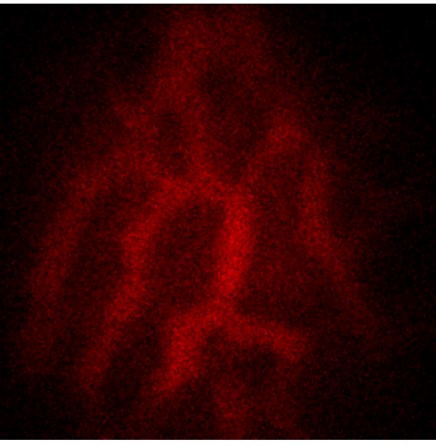

Zebrafish animal models were cultivated, and we developed fish lines with highly reduced pigmentation. Reference imaging was conducted by conventional fluorescence microscopy. Retinal blood vessels and beta cells in the endocrine pancreas were imaged. This also served to verify that the circulation time of nanoparticular contrast agent within the blood stream was long enough to allow for imaging.

Blood vessels in the retina imaged by fluorescently labelled contrast agent

Photoacoustic signal in zebrafish embryo when the contrast agent is switched ON / OFF periodically.